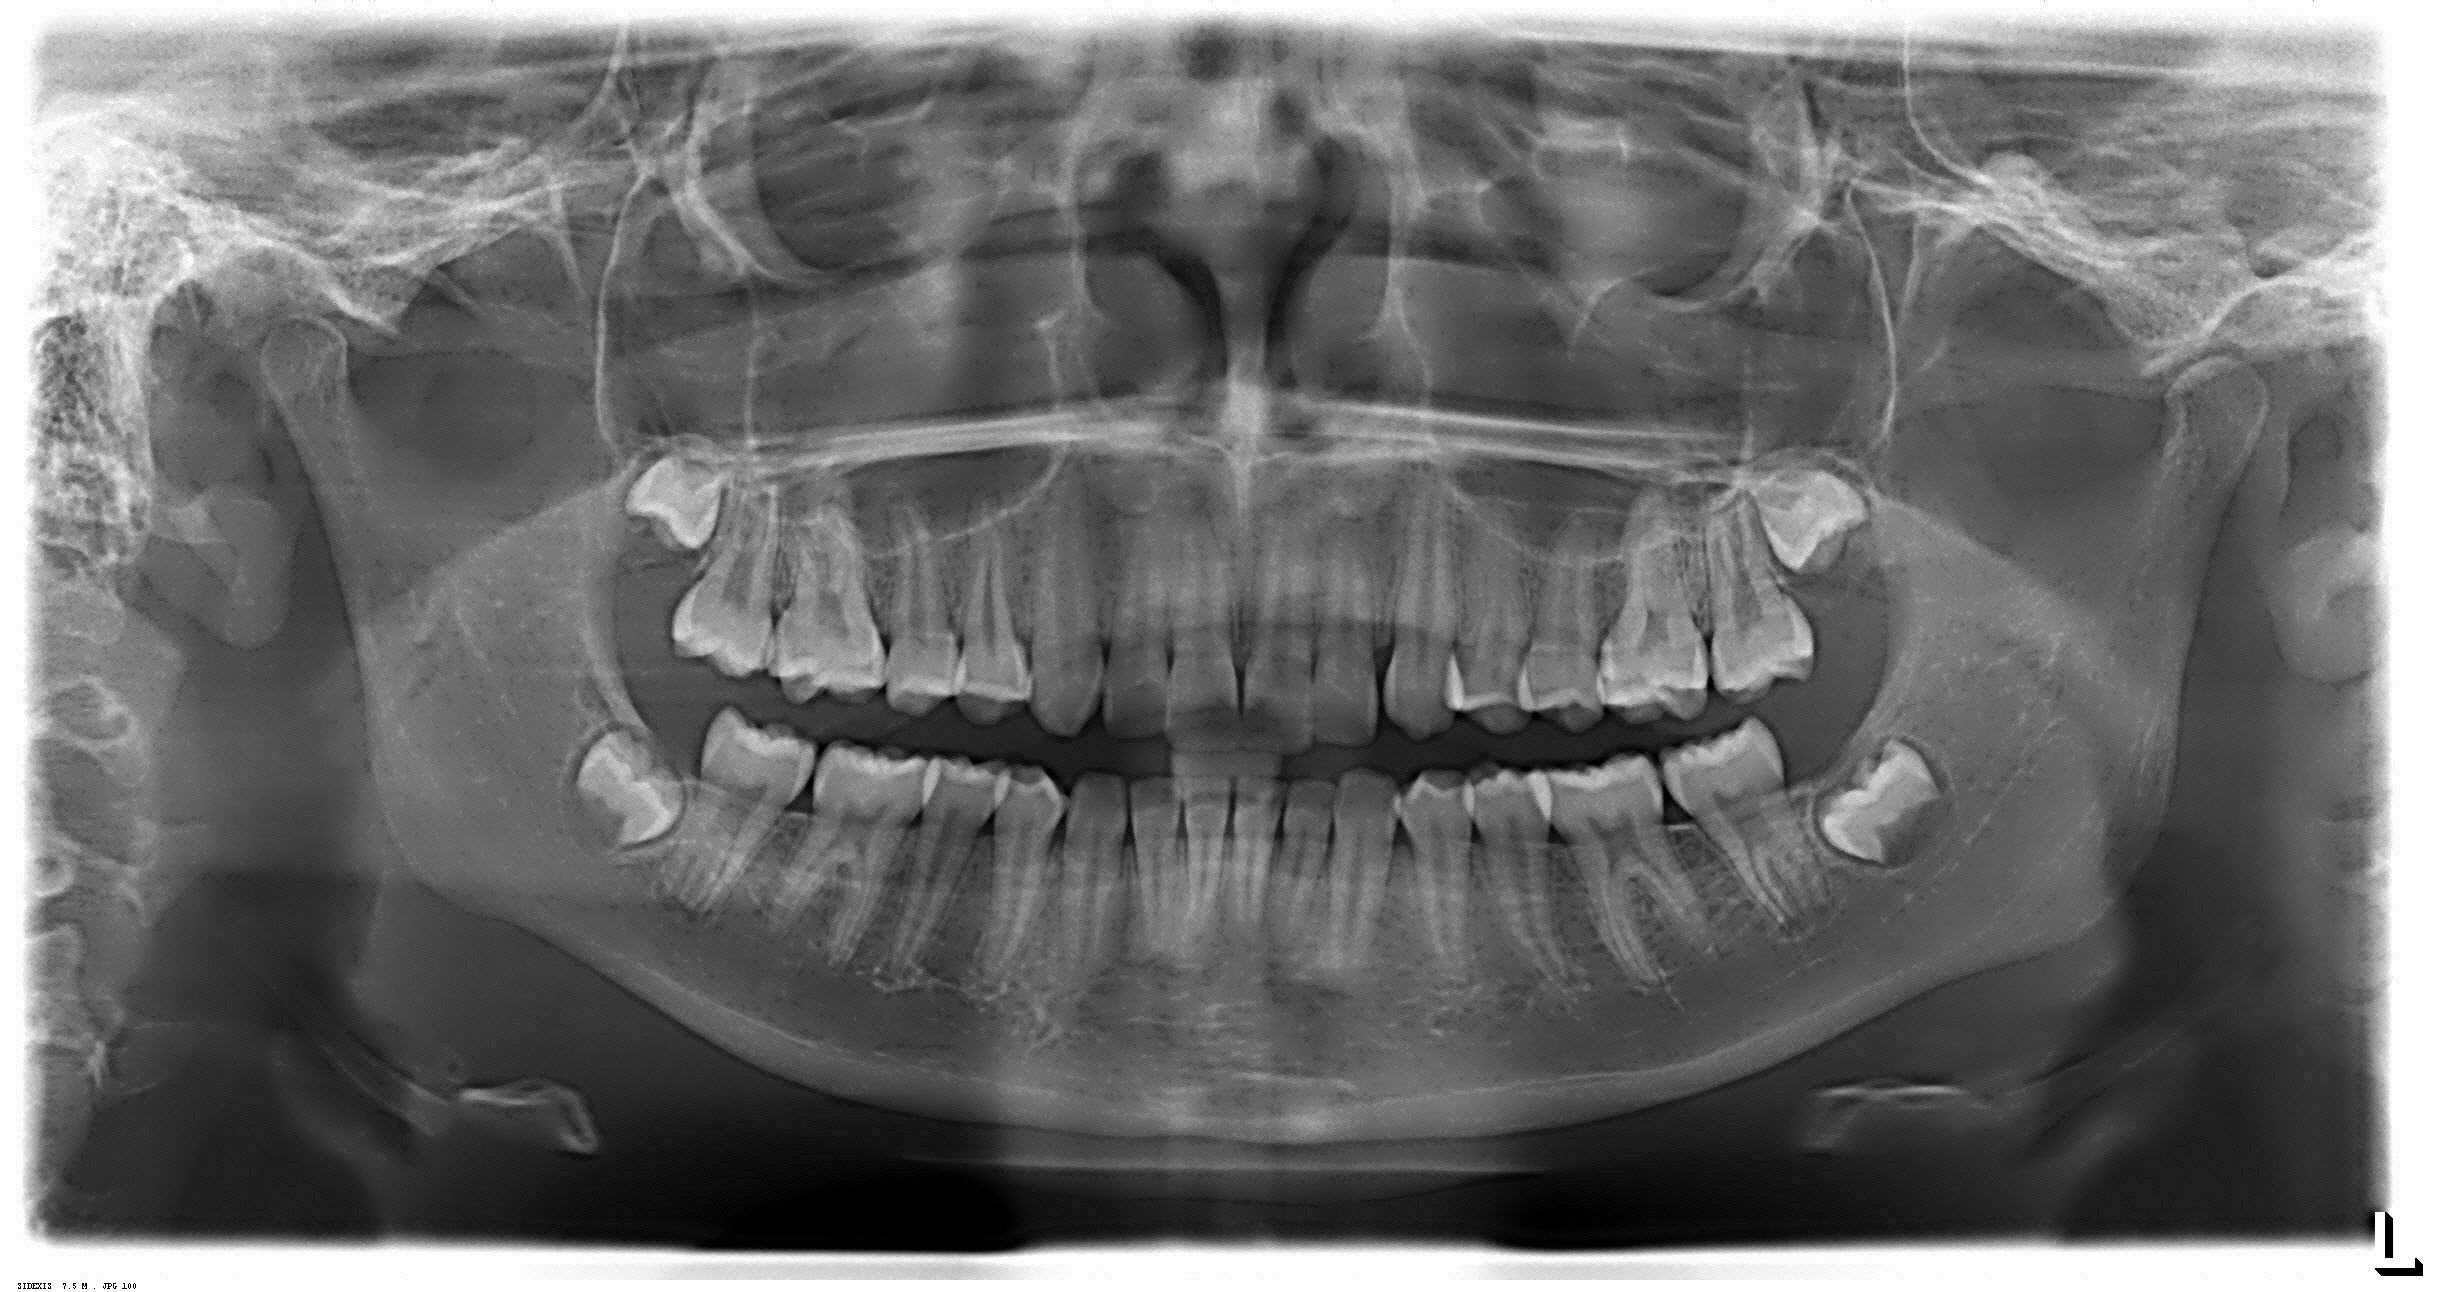

- Radiografia Panorâmica

Tomografia Computadorizada